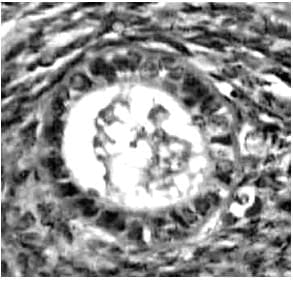

Molecular structure of FSH, LH and hCG.